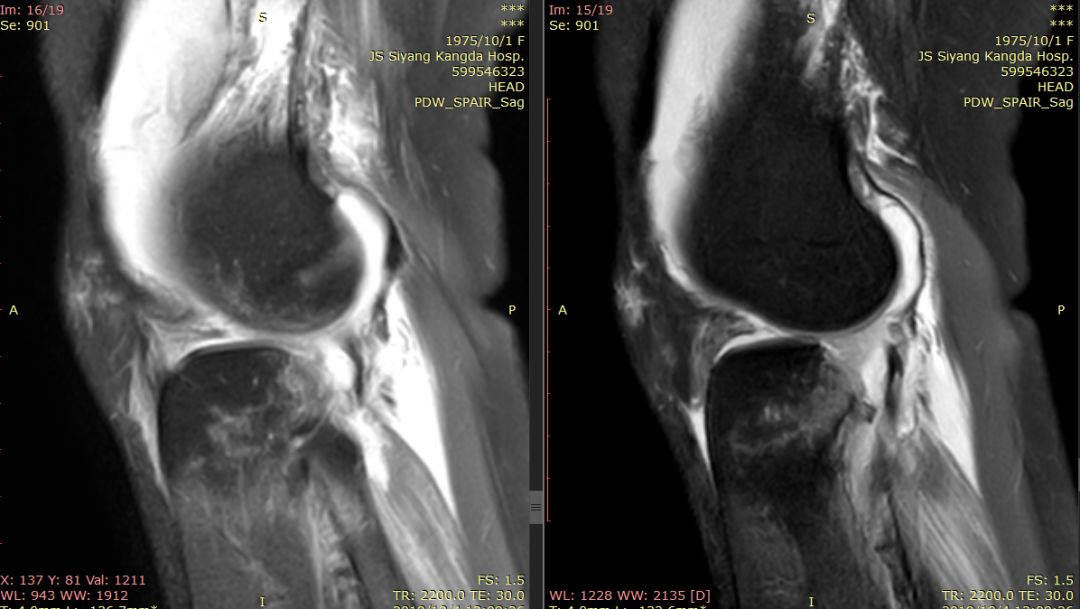

女44岁,外伤

前交叉韧带“消失”

外侧半月板后角“消失”